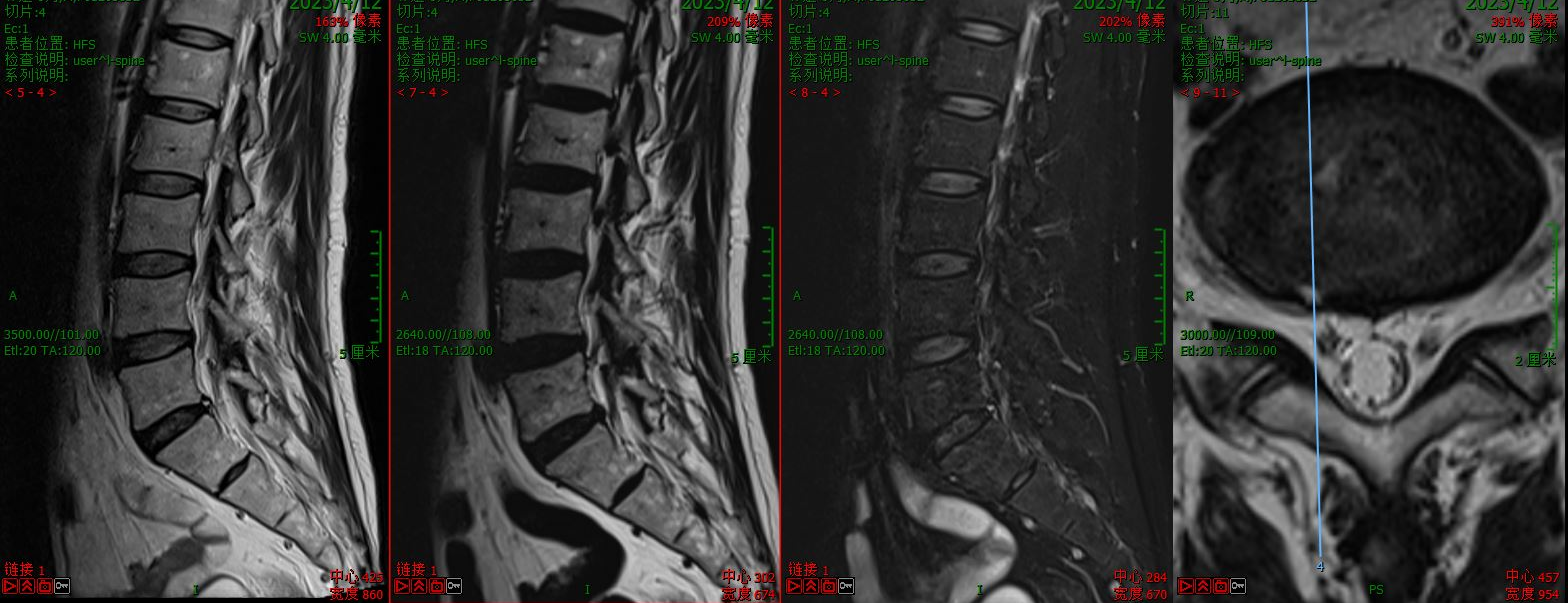

第一例病例为一名中年男性,腰4/5椎间盘突脱出并向下游离接近腰5/骶1椎间隙,为其实施VBE内镜下突出髓核单纯摘除术。患者术前腰痛伴右下肢疼痛麻木1个月余,右拇指背伸肌力明显下降。术后疼痛完全缓解,肌力较前部分恢复,有轻度麻木。

术前核磁